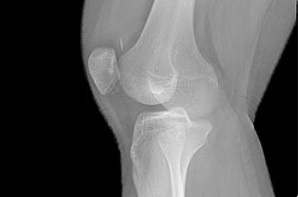

Надколенник — самая крупная сесамовидная кость скелета человека, располагающаяся в толще четырехглавой мышцы бедра. Кость прекрасно доступна для исследования и пальпации. Главной функцией надколенника является защита коленного сустава от боковых смещений и от механических ударов спереди.

Если была нанесена сильная механическая травма, коленный сустав отечный и возникают подозрения на вывих надколенника, то самостоятельно убедиться в правильности диагноза просто: визуально надколенник будет смещен, особенно, если сравнивать здоровую и поврежденную конечность. Не стоит забывать, что даже при условном его правильном нахождении надколенник может быть поврежден; речь идет о переломе.